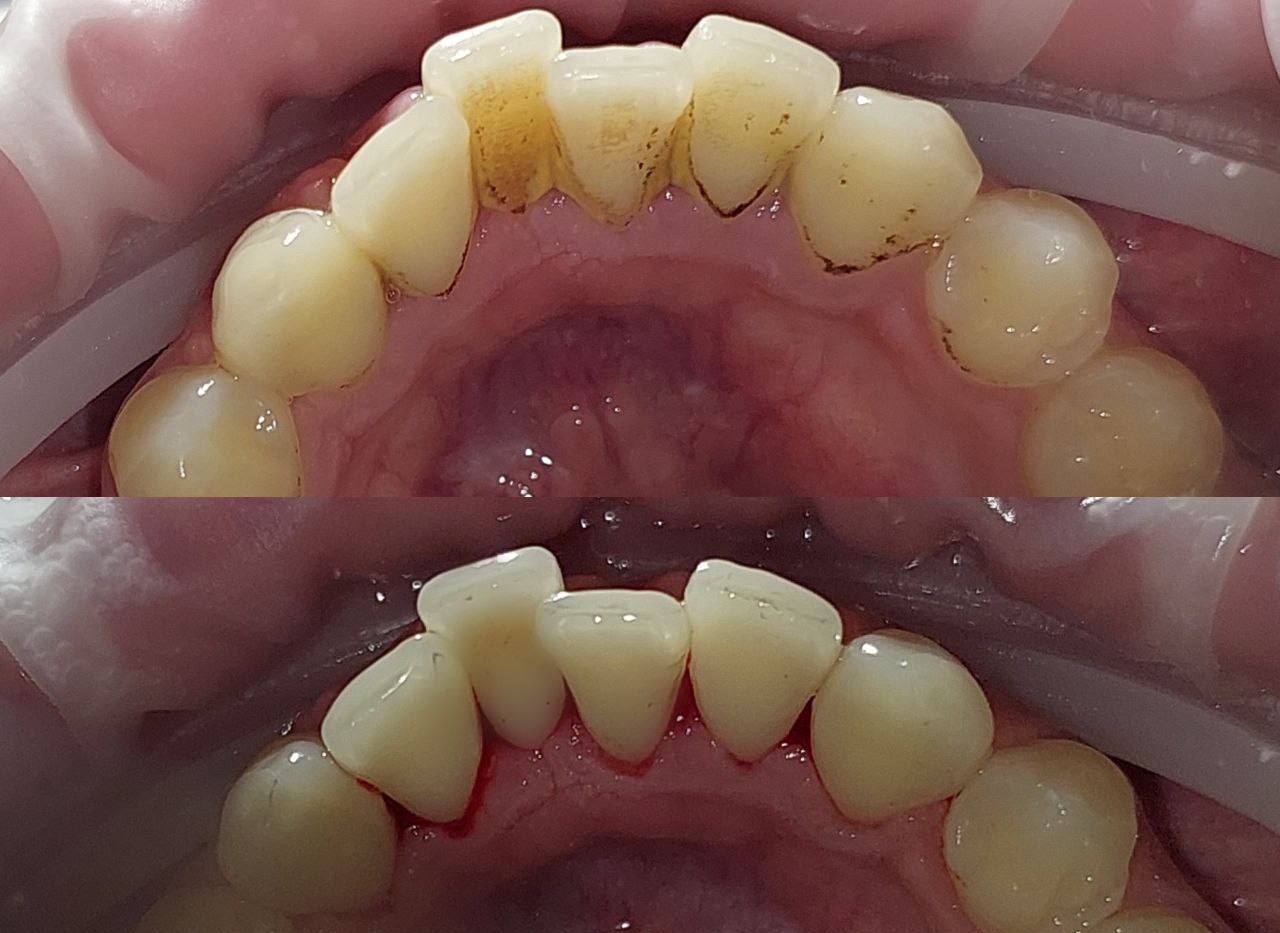

🦷Зубной налет — это липкая мягкая пленка, состоящая в основном из бактерий и продуктов их жизнедеятельности, смешанных с остатками пищи, белками из слюны, отмершими клетками слизистой оболочки, лейкоцитами и полисахаридами, формирующаяся на эмали зубов. Если его вовремя не удалять, он минерализуется и превращается в твердый зубной камень.

Со временем налет затвердевает из-за минерализации солями слюны, превращаясь в зубной камень.